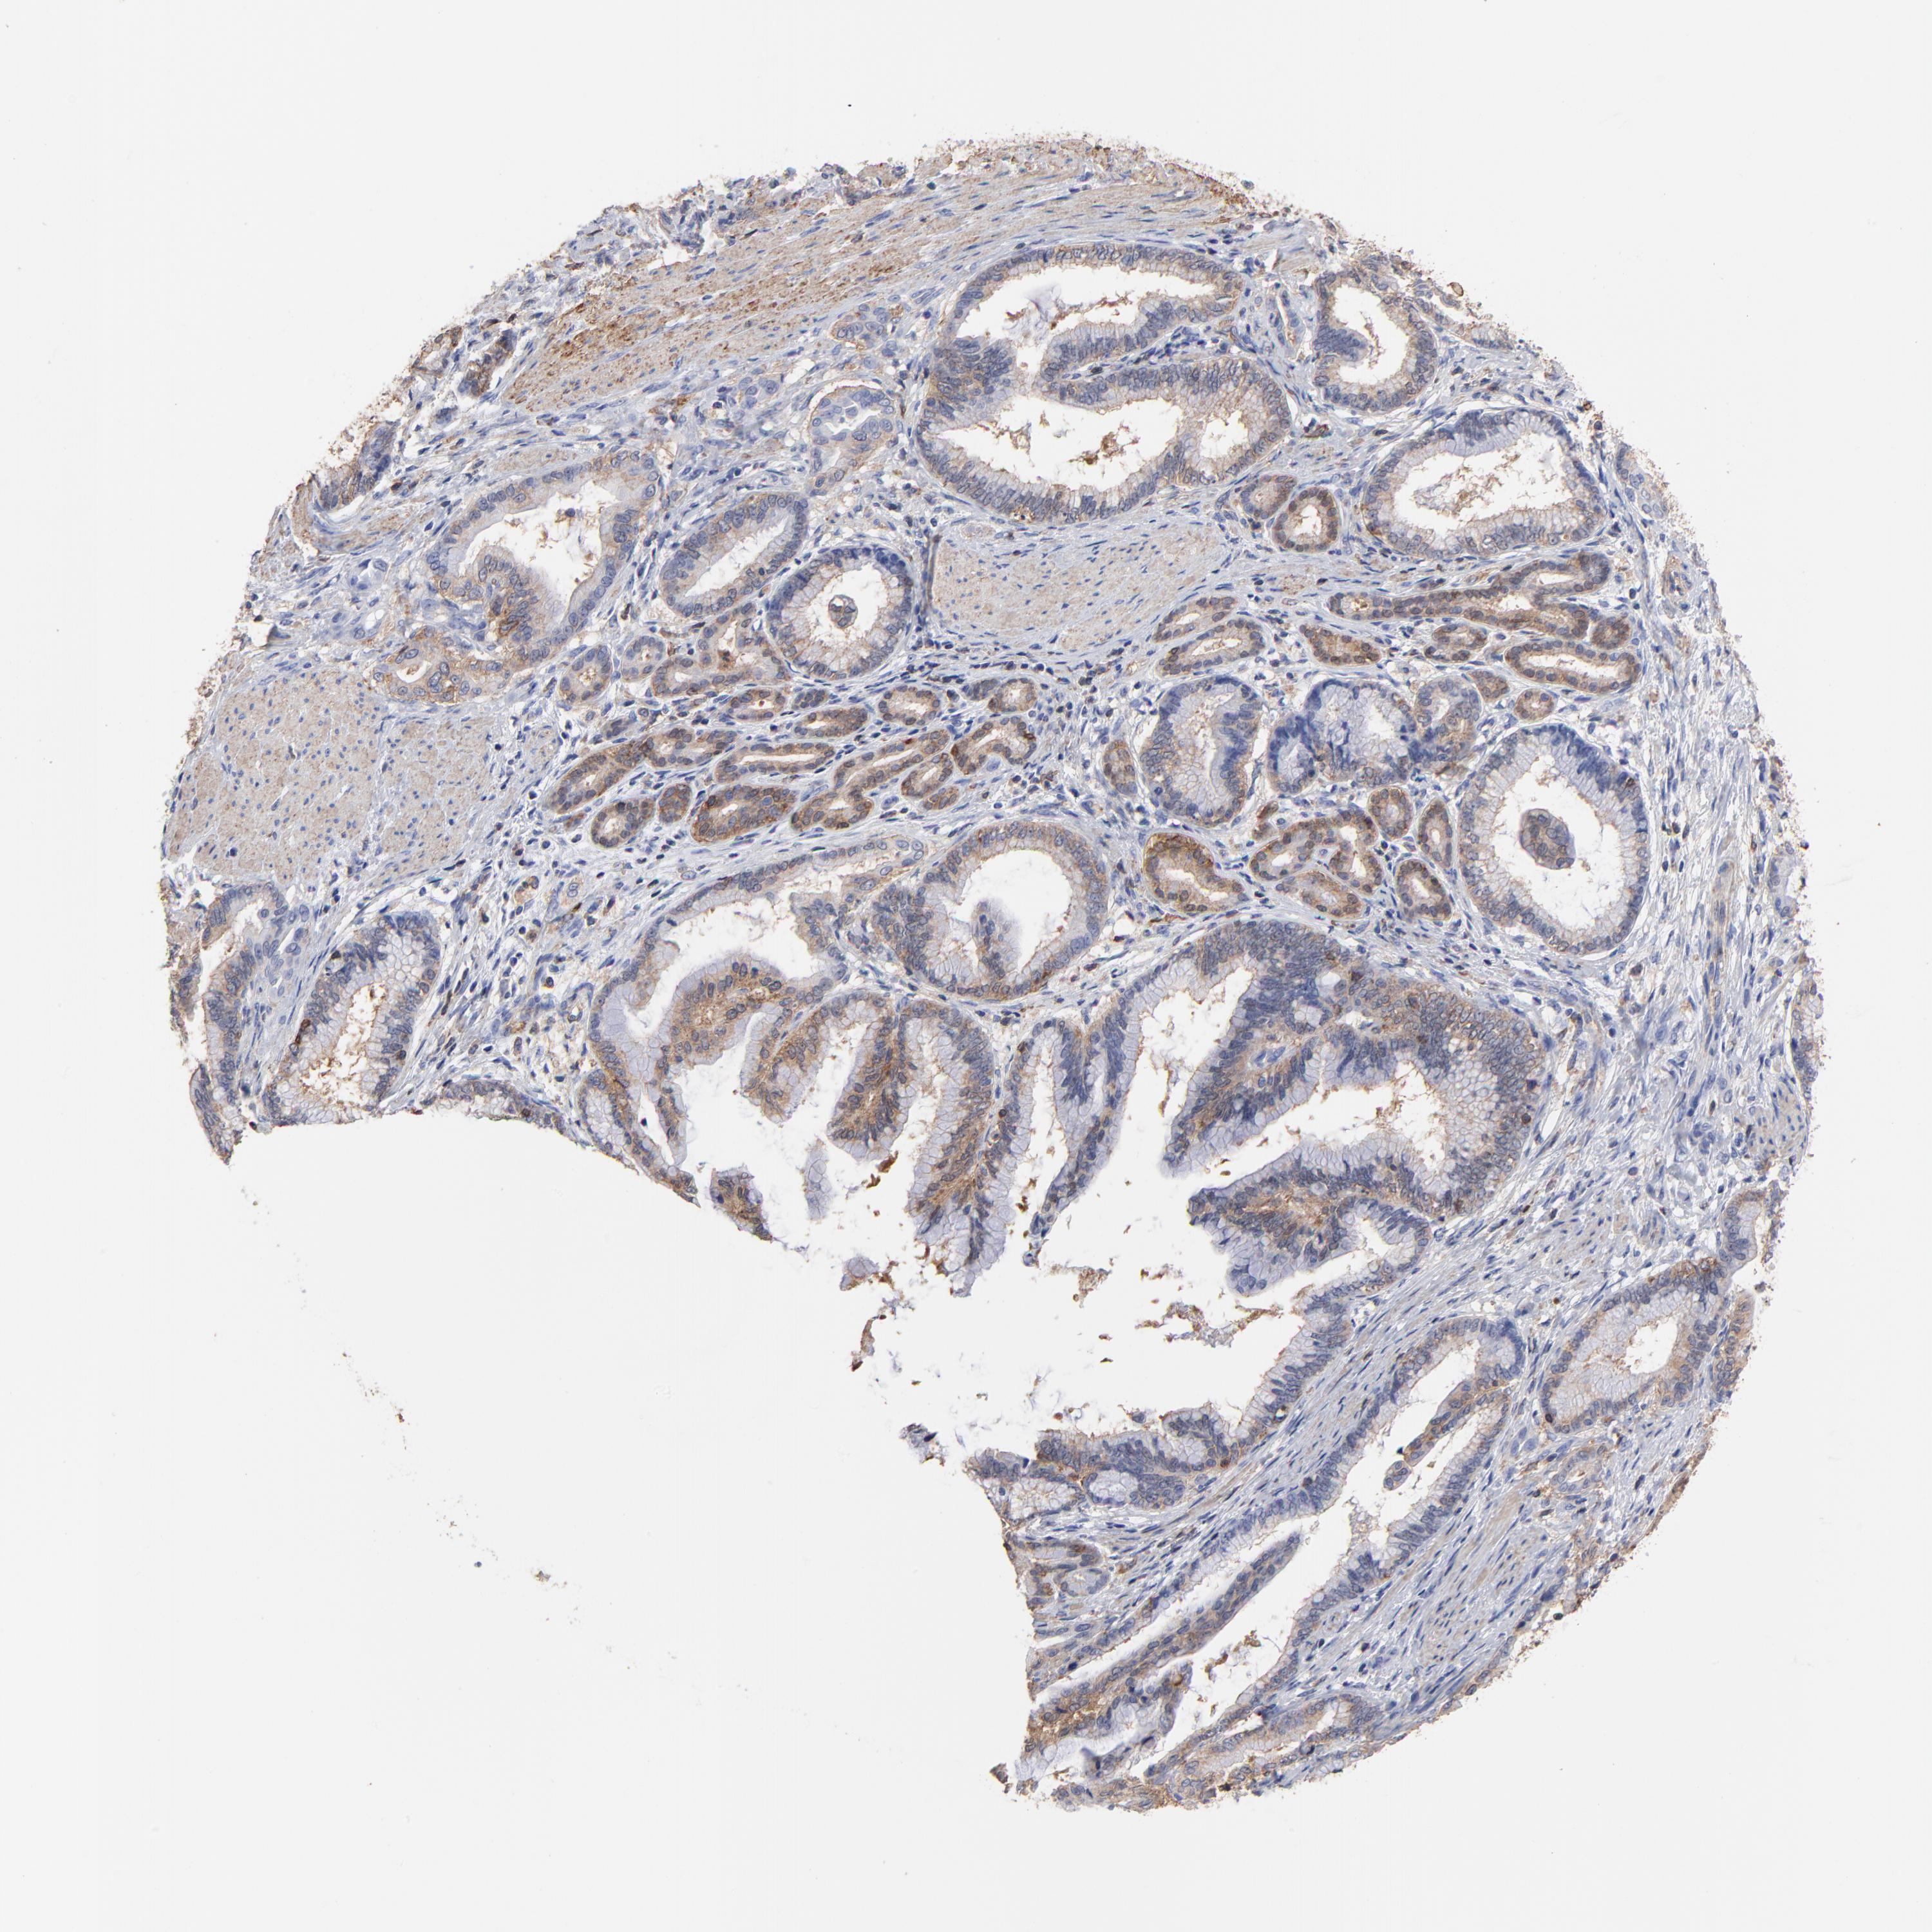

PANCREATIC CANCER - Protein expressioni

A mouse-over function shows sample information and annotation data. Click on an image to view it in a full screen mode. Samples can be filtered based on level of antibody staining by selecting one or several of the following categories: high, medium, low and not detected. The assay and annotation is described here.

Note that samples used for immunohistochemistry by the Human Protein Atlas do not correspond to samples in the TCGA dataset.

Antibody stainingi

Antibody staining in the annotated cell types in the current human tissue is reported as not detected, low, medium, or high, based on conventional immunohistochemistry profiling in selected tissues. This score is based on the combination of the staining intensity and fraction of stained cells.

Each image is clickable and will lead to virtual microscopy that enables deeper exploration of all samples and also displays staining intensity scores, fraction scores and subcellular localization as well as patient and tissue information for each sample.

Antibody HPA016646

Antibody CAB003696

Staining

High

Medium

Low

Not detected

Intensity

Strong

Moderate

Weak

Negative

Quantity

>75%

75%-25%

<25%

None

Location

Nuclear

Cytoplasmic/membranous

Cytoplasmic/membranous,nuclear

Adenocarcinoma, NOS

Adenocarcinoma, metastatic, NOS